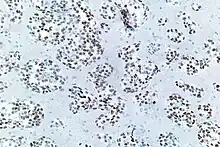

TTF-1 positive cells are found in the lung as type II pneumocytes and club cells. In the thyroid, follicular and parafollicular cells are also positive for TTF-1.

For lung cancers, adenocarcinomas are usually positive, while squamous cell carcinomas and large cell carcinomas are rarely positive. Small cell carcinomas (of any primary site) are usually positive. TTF1 is more than merely a clinical marker of lung adenocarcinoma. It plays an active role in sustaining lung cancer cells in view of the experimental observation that it is mutated in lung cancer.[11][12][13][14]

However others have found that TTF-1 staining is often positive in pulmonary adenocarcinomas, large cell carcinomas, small-cell lung carcinomas, neuroendocrine tumors other than small-cell lung carcinomas and extrapulmonary small-cell carcinomas.[16]

- ↑ Image by Mikael Häggström, MD. Source for significance: Bejarano PA, Mousavi F (2003). "Incidence and significance of cytoplasmic thyroid transcription factor-1 immunoreactivity". Arch Pathol Lab Med. 127 (2): 193–5. doi:10.5858/2003-127-193-IASOCT. PMID 12562233.